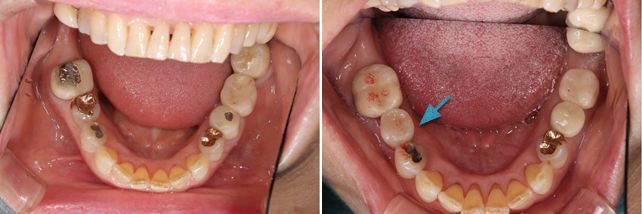

術前術後です。奥歯2本をオールセラミックインレーで治療しました。手前の銀歯はダイレクトボンディングを行いました。

セラミックインレー

費用11万円

リスクとして歯を削る量が多いため痛みが出る可能性と強い力によって割れる可能性がある。

ダイレクトボンディング

費用5万円

リスクとして欠ける可能性がある(修復可能)。